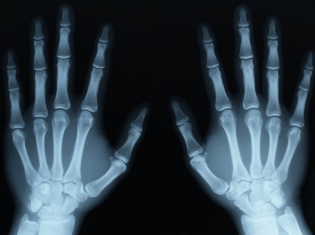

Many of these hand injuries are common to blue collar workers and include getting fingers caught in presses or rolling machines, hand injuries while doing home automotive work or those that happen in home construction projects that often involve power tools.

About 12 percent of traumatic injuries treated in hospital emergency rooms are wrist, hand or finger injuries, according to the study.